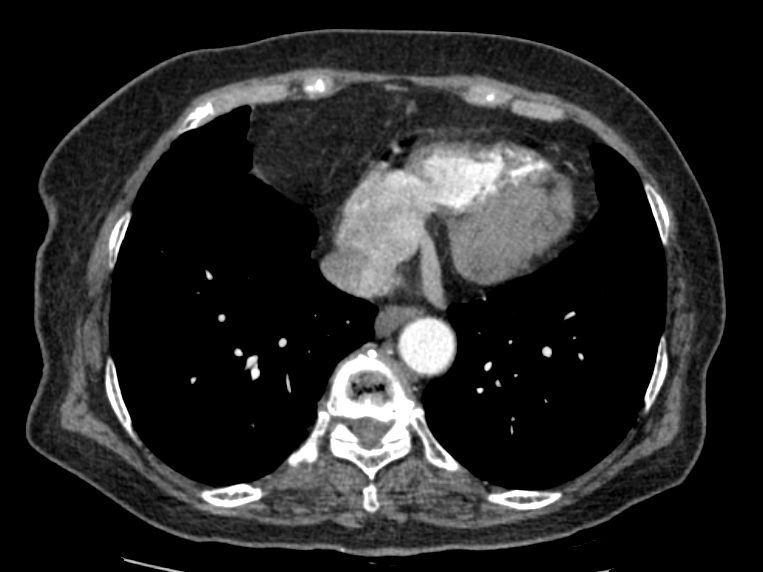

< Chest CT >